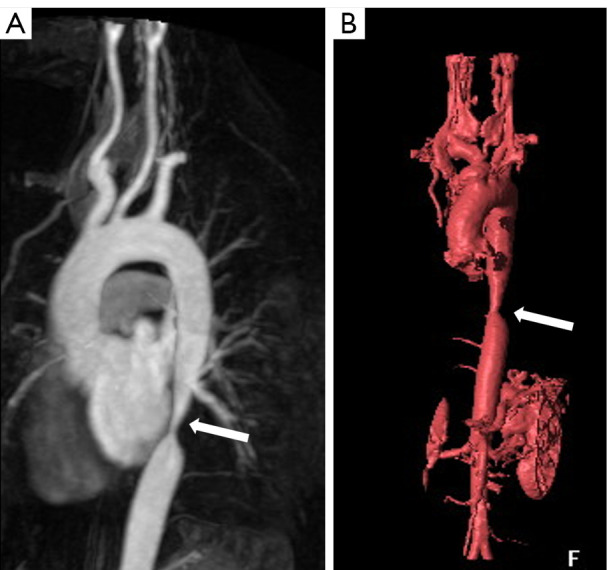

Abstract Image